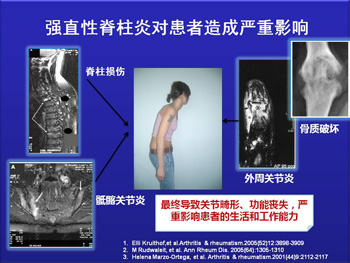

怎样预防强直性脊柱炎的危害?需做好以下三点

说起强直性脊柱炎,很多朋友都只知道这是一种骨科疾病,会导 ...

成都强直专科医院,大家要认真对待强直性脊柱炎的预防工作

面对强直性脊柱炎疾病的发生,强直性脊柱炎病人的生活平衡和和谐 ...